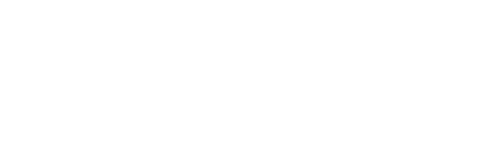

Im allgemeinen Sprachgebrauch auch Kniegelenksverschleiß genannt. Es handelt sich um eine fortschreitende Zerstörung des Gelenkknorpels unter Mitbeteiligung des Knochens, der Gelenkkapsel sowie der gelenkum- gebenden Muskulatur. Weitere Ursachen sind: angeborene Fehlstellungen des Kniegelenks („X-, O-Beine“), Bänderschwächen, Übergewicht, Stoffwechselerkrankungen, Infektionen, chronische Überlastungen im Sport oder im Beruf, Unfallfolgen (Knochenbrüche, Meniskus und Kreuzbandverletzungen), Knieerkrankungen im Kindesalter (Morbus Schlatter, Morbus Blount, Osteochondrosis dissecans) und/oder im Verlauf eines entzündlichen Rheumas. 10 % der Gesamtbevölkerung sind betroffen. Meist liegt die Gonarthrose beidseitig vor. Beginn im 4. Lebensjahrzehnt. Altersgipfel ist das 60. Lebensjahr.

Symptome: Schmerzen bei Belastung, zunehmende Instabilität und Bewegungseinschränkung, Schwellneigung, Gelenkerguss, Einschränkungen der Gehstrecke, Reibegeräusche, hinkendes Gangbild, Rückbildung der Beinmuskulatur.

Diagnostik: Röntgen der Kniegelenke in 2 bis 3 Ebenen: Aufhebung, Sklerosierung der Gelenkspalten, Knochenanbauten, Zystenbildung. Magnetresonanztomographie (MRT) zur Darstellung der Muskeln, Sehnen, Knorpel, Menisken, Kreuz- und Seitenbänder.

Therapie: Reduktion und Vermeidung von Überanstrengung und Fehlbelastung im Alltagsleben, Beruf und Sport. Kniegelenksinjektionen, begleitende medikamentöse Behandlung (entzündungshemmende, schmerzlindernde Tabletten). Im akuten Stadium lokale Kälte-, bei chronischen Stadien Wärmeanwendungen. Krankengymnastik und Manualtherapie (Mobilisierung, Muskeldehnungen, Beseitigung von Muskeldefiziten, Stabilisierung der Oberschenkelmuskulatur), Elektrotherapie oder auch Akupunktur. In jüngster Zeit hat sich der Gelenkflüssigkeitsersatz gut bewährt. Dabei wird durch Injektion von Hyaluronsäure neue „Gelenkschmiere“ bereitgestellt.

Prognose: Der Verlauf der Erkrankung ist meist progredient. Sehr häufig ist eine Operation notwendig. Gelenkerhaltende Operationen (Femur- oder Tibiakopf-Korrekturosteotomien) oder vollständiger oder teilweiser Gelenkersatz (Endoprothese). Individuelle Planung der zu wählenden Implantate und Materialien. Eigenblutspende. Postoperative Physiotherapie, frühzeitige Mobilisierung und Belastungsaufbau. Aufklärung über erlaubte Bewegungen und Belastbarkeit. Regelmäßige klinische und röntgenologische Nachkontrollen.